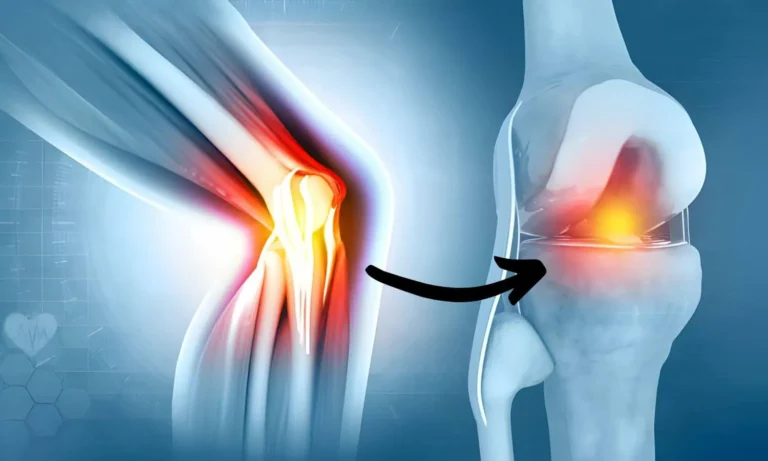

A groundbreaking medical discovery is challenging everything we’ve been taught about joint pain and aging.

According to researchers linked to Harvard and Cambridge, the real reason behind stiff, sore, cracking joints has very little to do with cartilage “wear and tear” — and almost everything to do with what scientists now describe as joint hydration loss, sometimes referred to as a “joint drought.”

As we age, the natural fluid that keeps joints cool, cushioned, and smoothly lubricated can begin to dry out. When this happens, joints lose their ability to glide properly, leading to friction, inflammation, and that familiar morning stiffness that makes getting out of bed, climbing stairs, or even opening jars feel like a daily struggle.

Most people are told this discomfort is simply part of getting older. But new research suggests that explanation may be incomplete — and that the problem may not be irreversible.